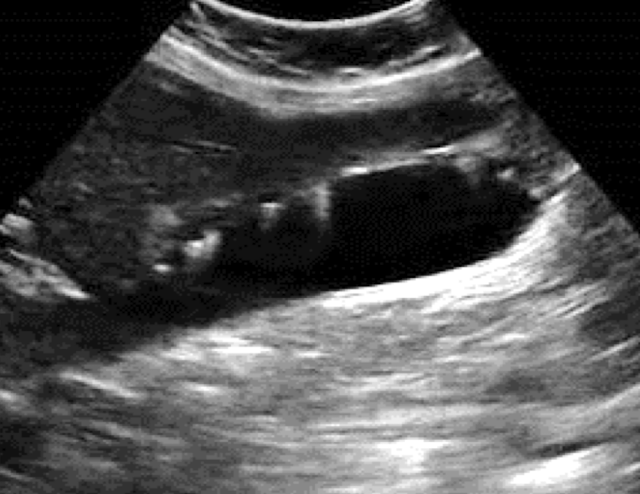

SONO: emphysematous cholecystitis

bright echoes along anterior GB wall with “ring down” or “comet tail” artifact

gallstones may not be present

??

emphysematous cholecystitis

“ring down” artifact